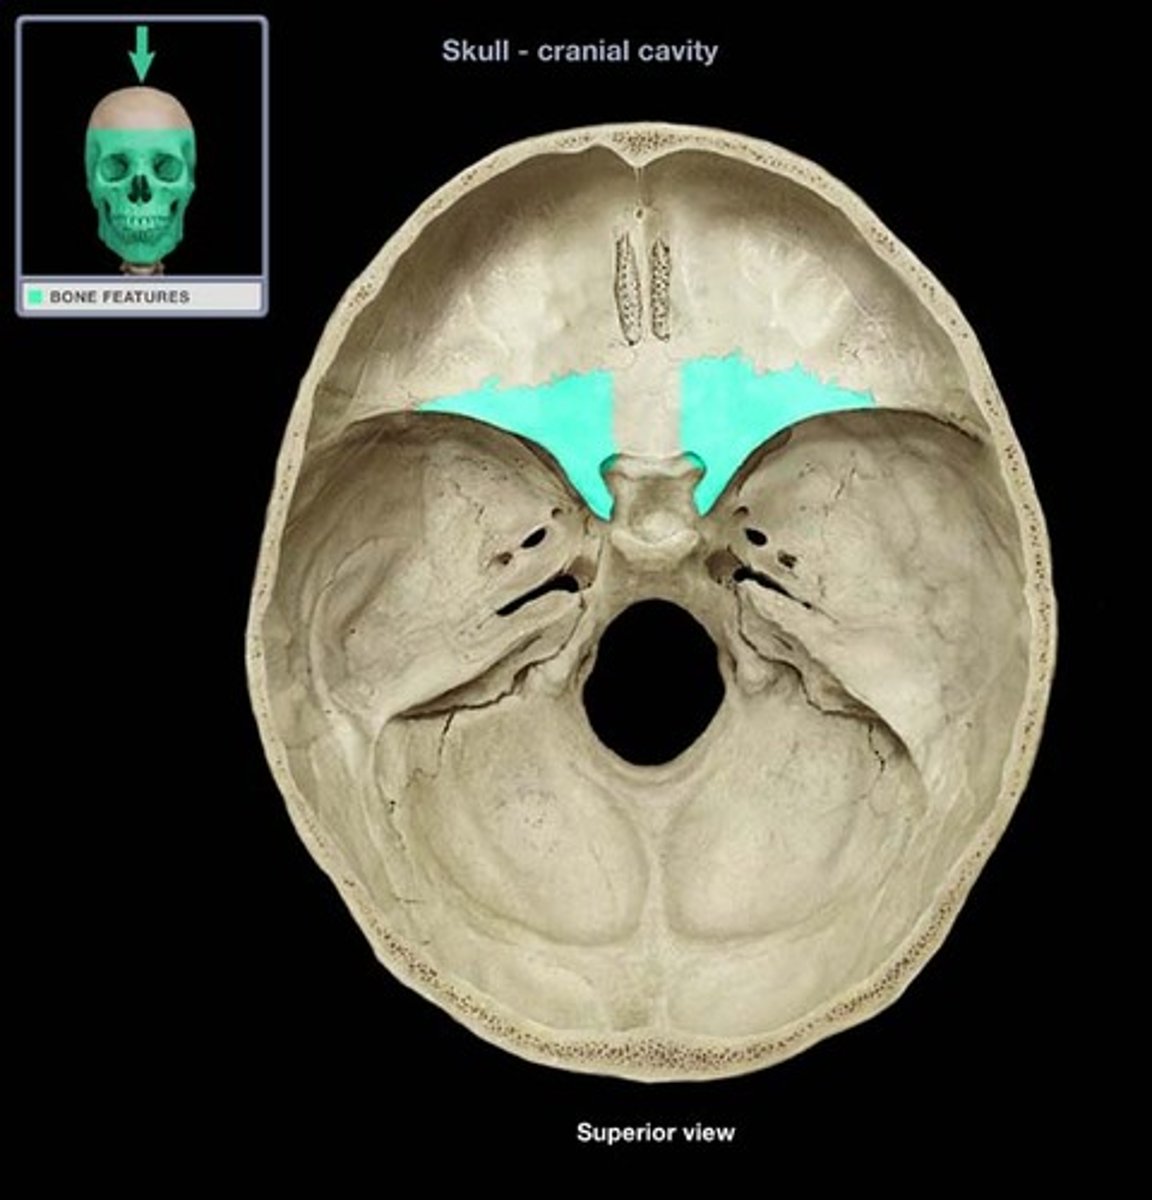

anterior cranial fossa

cribriform plate

crista galli